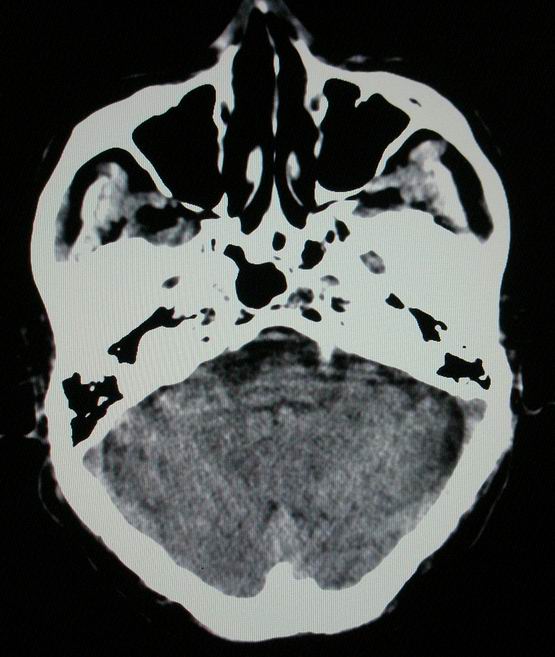

以下是引用随光逐影在2008-4-5 7:46:00的发言:[br]1)考虑为:多发性脑转移瘤。建议:行进一步检查。2)多发性腔隙性脑梗塞。3)脑白质病。4)脑萎缩。

以下是引用zjzjr在2008-4-5 9:00:00的发言:[br]1.双侧颞叶占位性病变,考虑为转移瘤可能性大。[br]2.左侧基底节区陈旧性腔隙性脑梗塞。[br]3.脑白质病。建议mri进一步检查。

以下是引用xuhuihong在2008-4-5 0:59:00的发言:[br]1.双侧颞叶占位性病变,考虑为转移瘤可能性大。[br]2.左侧基底节区陈旧性腔隙性脑梗塞。[br]3.脑白质病。建议mri进一步检查。

以下是引用形影不离在2008-4-4 23:29:00的发言:[br]1.双侧颞叶占位性病变,考虑为转移瘤可能性大。[br]2.左侧基底节区陈旧性腔隙性脑梗塞。[br]3.脑白质病。